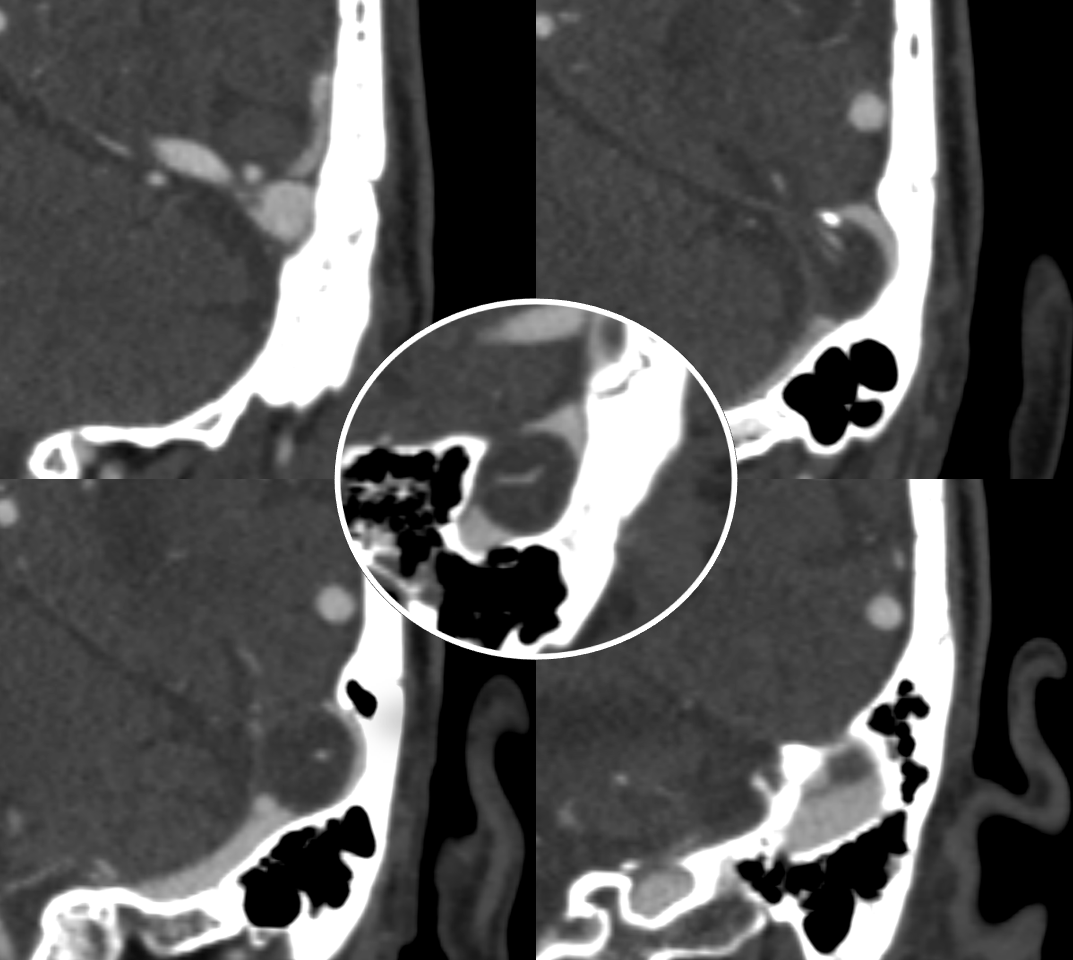

All of the above anatomic knowledge can become very useful in evaluation of venous thrombosis. Numerous collateral pathways develop in this setting attempting to compensate for the loss. The most dramatic cases usually involve the largest channel — the superior sagittal sinus. In this case, a man presented with what initially was thought to be vasculitis-related brain hemorrhage. Subsequent workup led to an angiogram, where sagittal sinus thrombosis with extensive trans-cerebral and trans-osseous emissary vein collateral channels was seen. In retrospect, these findings were present on the patient’s earlier contrast MRI. “Venovibe” or other contrast-enhanced MR venograms can very sensitive, particularly when interpreted with the appropriate index of suspicion. Noncontrast 2-D time of flight MRV I consider to be next to useless as a problem-solving technique. Any thin-slice postcontrast T1 study is vastly superior.

NOT ALWAYS ASYMPTOMATIC! — here is left frontal convexity cortical venous thrombosis in veins emptying into SSS at level of giant granulation. Very likely related. Granulation is in middle upper row image. Full case (angios etc) here.